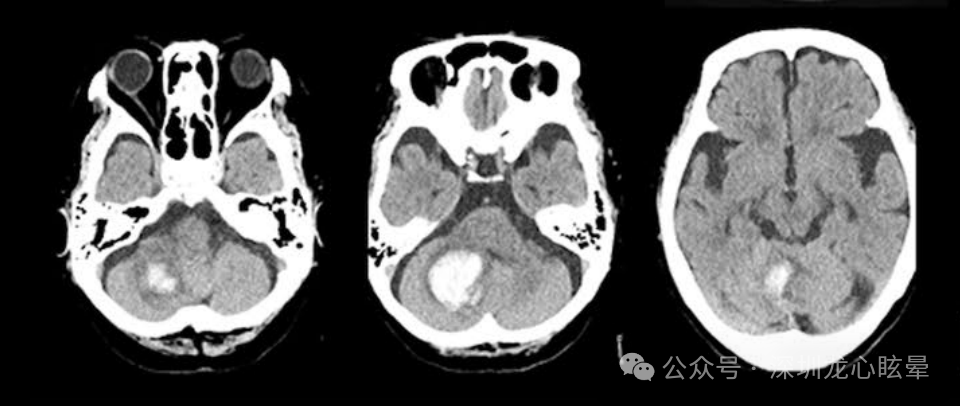

小脑病变引起的中枢血管源性孤立性眩晕:最常受累的血管是小脑后下动脉(posterior inferior cerebellar artery , PICA)和小脑前下动脉(anterior inferior cerebellar artery , AICA),而小脑上动脉(superior cerebellar artery , SCA)供血区病变颇为少见。由 PICA 供血的小脑小结叶、扁桃体、小脑下脚;由AICA 供血的前庭神经核、前庭神经入颅处、绒球以及由基底动脉供应的舌下神经前置核(NPH)等部位的孤立性梗死均可导致孤立性眩晕。

图2 一例右侧小脑急性脑梗死

(1)PICA供血区: 小脑小结、小舌及扁桃体受累均可表现孤立性眩晕和姿势平衡障碍,其中以小结病变引起的孤立性中枢性前庭综合征最为常见。小结损害可造成同侧前庭神经核失抑制、速度储存机制调控及空间定位功能异常,可以发现快相朝向病灶侧的水平自发眼震、倒错性摇头眼震、病理性眼偏斜反应及主观垂直视觉偏斜等体征;小舌与扁桃体病变可以发现单向凝视诱发眼震与倒错性摇头眼震,小舌病变还可见异常的视动性眼震,而朝向病灶侧平稳跟踪受损可见于单侧扁桃体病变。头脉冲试验是识别表现为“假性前庭神经炎”的PICA内侧支梗死最有效的床旁检查手段,其检查结果通常为阴性。

(1)孤立性小脑小结梗死:小脑小结由 PICA 供血,位于小脑的中线部位,它与同侧前庭神经核有着密切联系,同时接受来自迷路的传入信号,控制眼动并调节姿势平衡。孤立的小结梗死非常少见,查体可见单向自发眼震以及向健侧倾倒。自发眼震的方向朝向患侧,还可出现周期交替性眼震、倒错摇头眼震和阵发性中枢性位置性眼震等表现。这与小结对重力惯性的前庭信号处理、前庭二级神经元的抑制功能和速度储存机制受损有关。大部分小结梗死临床表现与急性前庭外周病变类似,但其 HIT和双温试验正常、严重的姿势不稳是与前庭外周病变的重要鉴别点。

(2)孤立性小脑扁桃体梗死:孤立的小脑扁桃体(PICA 供血)梗死罕见,其表现为以下体征:①方向向患侧的自发眼震;并出现反跳性眼震;②GEN,向患侧注视时强度更大;③平稳跟踪损害;④双温、HIT、前庭眼反射、扫视正常。部分患者还出现主观垂直视觉向健侧偏斜,提示扁桃体不仅与半规管通路的张力不平衡(导致自发眼震)有关,而且对耳石系统也有一定的控制作用。

(3)孤立性小脑下脚(ICP)梗死:ICP包含了出入小脑的各种纤维,主要整合本体感觉和前庭的信息。前庭小脑到前庭神经核的传入和传出纤维都经过ICP,所以孤立性ICP损伤表现为眩晕和姿势不稳。主要表现为向患侧的自发眼震,患侧平稳跟踪异常,健侧 OTR 和主观垂直视觉偏斜。

(4)孤立性小脑绒球梗死:小脑绒球参与控制凝视稳定、平稳跟踪和前庭刺激诱发的眼动。单纯绒球梗死少见,症状为突发眩晕和姿势不稳;查体自发眼震朝向患侧,无眼扭转、头偏斜及主观垂直视觉偏斜。HIT 显示健侧轻度纠正性扫视,双温试验无异常。在转椅检查中,低频水平刺激时前庭眼反射增益增高,高频刺激时出现双侧前庭眼反射不对称的增益减低。